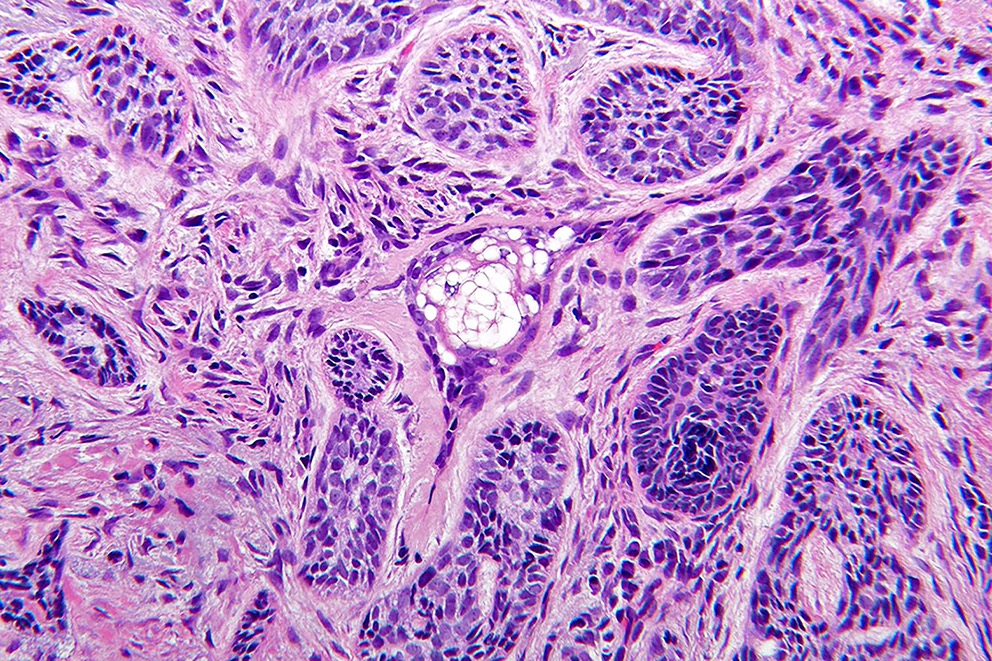

Common variants (Calonje: McKee's Pathology of the Skin, 5th Edition, 2019)

- Nodular and nodulocystic BCC

- Relatively circumscribed mass

- Epidermal or follicular attachment variably present

- Large basaloid lobules with peripheral nuclear palisade

- Lobules may be solid or show central cyst formation due to excessive mucin production

- Fibromyxoid stroma

- Cleft formation between tumor lobules and stroma

- Pleomorphism is generally mild

- Variable mitotic activity and apoptosis

- Sometimes necrosis en masse

Microscopic (histologic) images

Contributed by Antonina Kalmykova, M.D., Phillip H. McKee, M.D., Sate Hamza, M.D., Eduardo Calonje, M.D.,

Wayne Grayson, M.B.Ch.B., Ph.D., James Sampson, M.B.B.S., M.Sc. and Assia Bassarova, M.D., Ph.D.